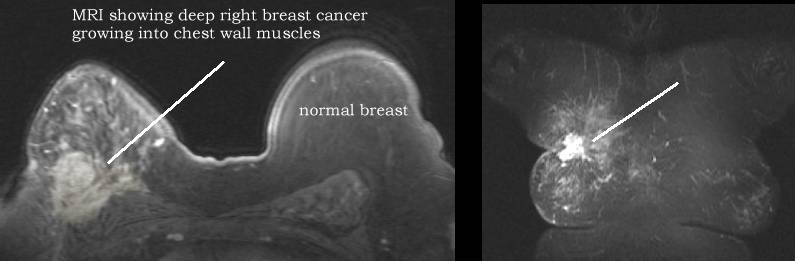

Breast MRI is playing an increasing role in imaging breast cancer see more pics Advanced stage: pic, pic, pic, pic, pic, pic, pic, pic, pic, pic, pic PET versus MRI here, here, here

Woman with benign lesion in right

breast cancer in left (go here) MRI may be useful in male breast cancer: see mammogram and MRI An MRI will show normal anatomy well (here) and is helpful in following women who have had surgery (here) and radiation (here). MRI of woman with previous cancer developed cancer in opposite breast (here) and woman with previous mastectomy with reconstruction developed recurrence in reconstructed breast (here) MRI is good for women have had previous breast implants (augmentation) go here |